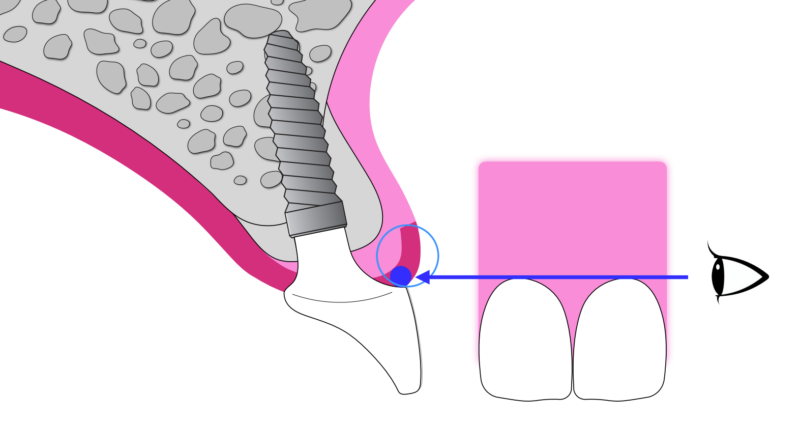

そこで近年注目されているのが、「抜歯と同時にインプラントを入れる方法」です。さらに、歯の一部をあえて残すことで歯肉や骨の形を維持する「ソケットシールドテクニック(SST)」という手法もあります。これにより、組織の吸収を最小限に抑え、より自然な仕上がりが期待できます。

①向かってる左のすぐにインプラントが可能な部分にはSSTを併用し、できるだけ負担の少ない治療を選択。